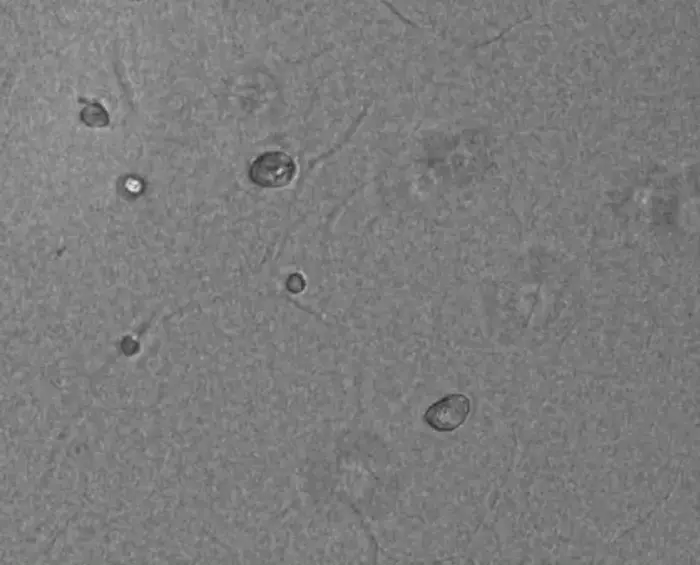

Human iPS cells grown within the laminin-511-functionalized fibrin gel

Credit: The University of Osaka

The research team has engineered a unique 3D culture system to overcome this limitation. They successfully integrated laminin-511, a protein crucial for stem cell adhesion and proliferation, into a fibrin-based gel. Fibrin is a natural, biocompatible protein, making it an ideal scaffold. The study demonstrated that human iPSCs can be successfully grown *within* this specialized gel, allowing them to proliferate in a 3D structure that more closely resembles how cells grow in living tissues. This method is expected to maintain the cells' viability and pluripotency more effectively than conventional techniques.